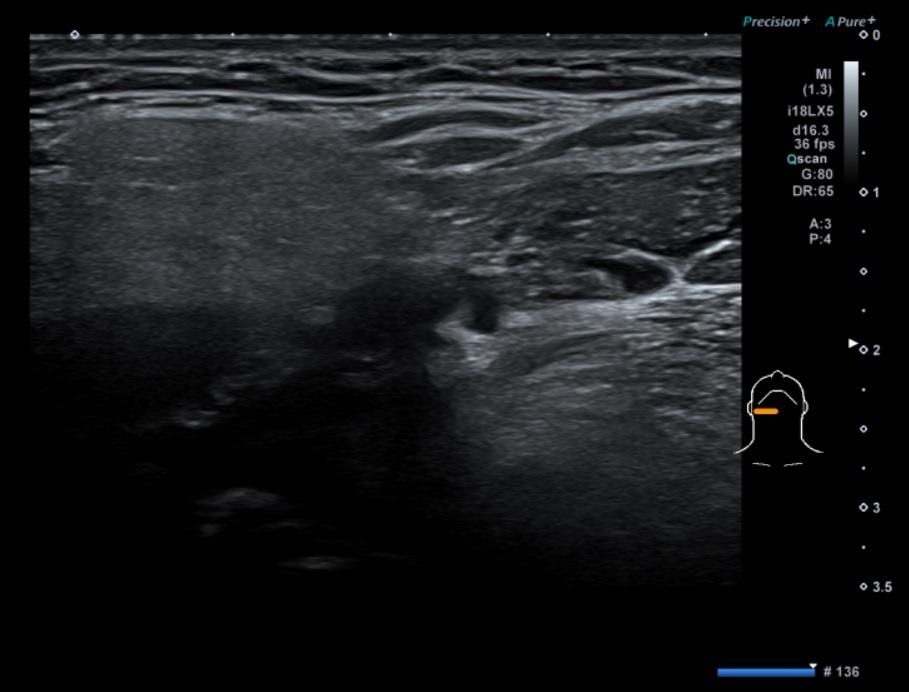

• 1번 째 사진